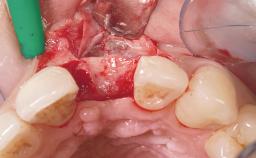

Immediate Placement of an Implant in a Maxillary Left Central Incisor Site

A 33-year-old female patient presented with an upper left central incisor that required extraction after a failed endodontic therapy. The tooth had been traumatized when the patient was a teenager and had undergone several endodontic treatments, including two apicectomy procedures. The patient was in good health and did not smoke. Clinical examination showed that the patient had a high lip line. In full smile, the gingival margins of the upper teeth were visible to the first molars. The gingival margins of central incisors 11 and 21 were only just showing. Examination of tooth 21 confirmed that the tooth was mobile and had hypererupted by 1 mm.

Bone Augmentation Horizontal|Simultaneous

Augmentation Materials Xenogenous|Membrane

Soft Tissue Grafting Simultaneous